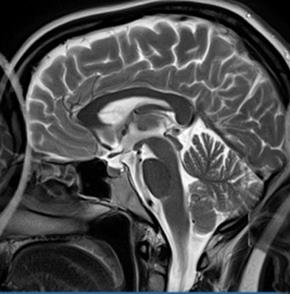

Którą strukturę anatomiczną oznaczono na obrazie rezonansu magnetycznego?

Ilustracja do pytania 15

A. Trzon kości ramiennej.

B. Guzek większy kości ramiennej.

C. Głowę kości ramiennej.

D. Guzek mniejszy kości ramiennej.